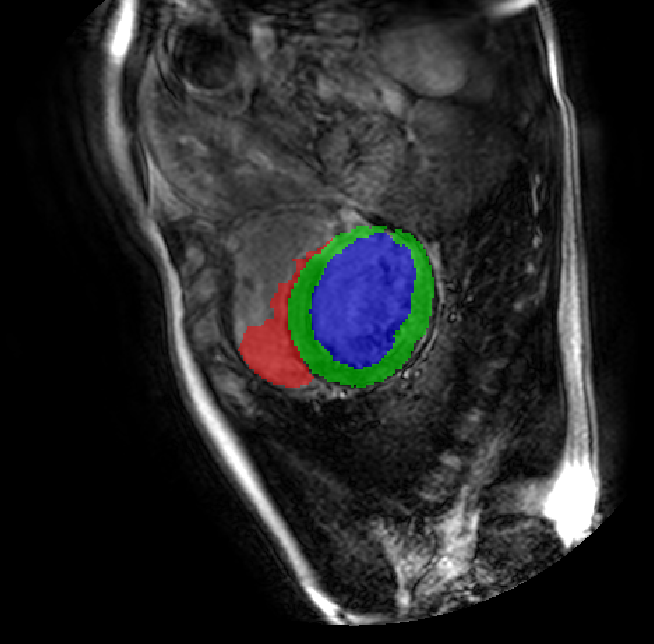

Table 2 presents an ablation study and compares SparseMamba-PCL with nine SOTA scribble-supervised methods across the three datasets. Out method achieves the highest Dice score across all the datasets, and the lowest (CHAOS) and second lowest (ACDC and MSCMRSeg) HD95 values, confirming its effectiveness in segmentation accuracy and boundary refinement. Baseline+SPOBE and Baseline+PCL improve upon the Baseline (SparseMamba), demonstrating the benefits of boundary-aware supervision and SAM-guided learning. Fig. 4 (l) compares the segmentation performance of SparseMamba-PCL with other scribble-supervised methods, showing smoother edges that precisely delineate object boundaries, unlike the jagged or blurred edges in other methods. The examples also demonstrate the consistent segmentation quality achieved by SparseMamba-PCL across ACDC, CHAOS, and MSCMRSeg, highlighting its adaptability across multiple medical domains. This adaptability and precise segmentation is crucial for accurate volumetric analysis and clinical decision-making, where even subtle boundary inaccuracies can lead to diagnostic errors. In summary, the SparseMamba-PCL architecture provides a consistent and robust improvement in segmentation metrics across diverse medical image datasets.

Refer to caption Refer to caption Refer to caption Refer to caption Refer to caption Refer to caption Refer to caption Refer to caption Refer to caption Refer to caption Refer to caption Refer to caption

(a) (b) (c) (d) (e) (f) (g) (h) (i) (j) (k) (l)

Figure 4: Qualitative comparison of weakly-supervised segmentation methods on ACDC, CHAOS, and MSCMRSeg datasets. (a) Input image, (b) ground truth, and segmentation results from (c) USTM [16], (d) Scribble2D5 [5], (e) CycleMix [26], (f) ShapePU [27], (g) S²ME [21], (h) ScribbleVC [12], (i) TDNet [30], (j) PacingPseudo [25], (k) Scribbleformer [13], and (l) SparseMamba-PCL are given.